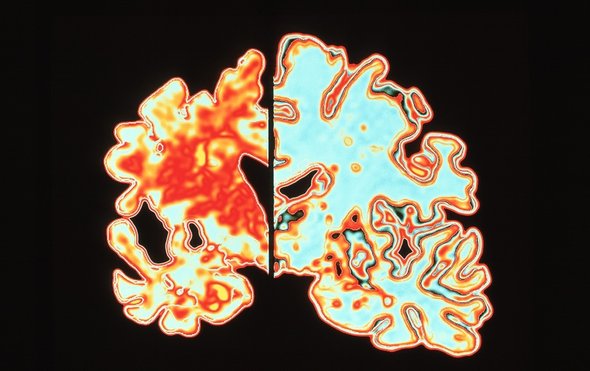

In their study, the LMU researchers confirmed the presence of magnetic particles in human brains. The particles were found primarily in the cerebellum and the brainstem, and there was striking asymmetry in the distribution between the left and right hemispheres of the brain. “The human brain exploits asymmetries in sensory responses for spatial orientation, and also for sound-source localization,” Schmitz explains. The asymmetric distribution of the magnetic particles is therefore compatible with the idea that humans might have a magnetic sensor. But in all probability, this sensor is much too insensitive to serve any useful biological function, he adds. Furthermore, the chemical nature of the magnetic particles remains unknown. “We assume that they are all made of magnetite (Fe3O4), but it is not yet possible to be sure,” says Gilder.